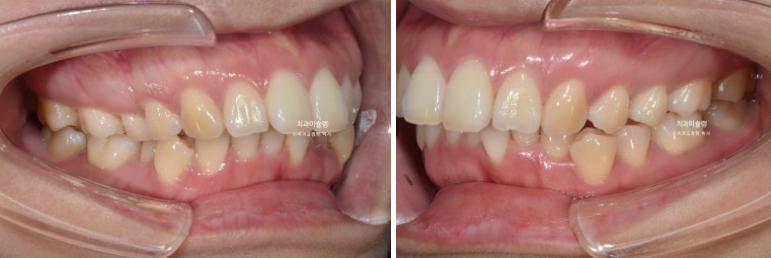

이제 전후 비교 보겠습니다.

총 치료기간은 3년 2개월, 재제작은 3회 했습니다.

2022.11~2026.01

어금니 교합은 뜨는 곳 없이 좋습니다.